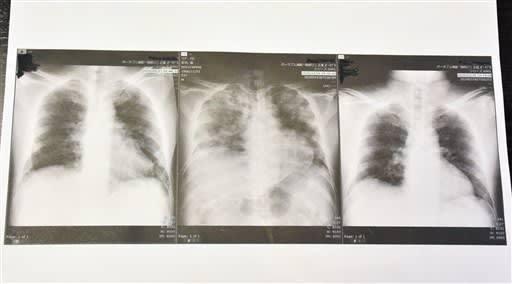

日本 胸片,揭秘胸片背后的健康奥秘

哎呀,你知道吗?最近我在网上看到一个超级有趣的话题,那就是日本的胸片文化。听起来是不是有点奇怪?别急,让我带你一起探索这个独特的现象,看看它背后隐藏的故事。一、日本胸片文化的起源说起胸片,你可能会想到医院里的X光片,但日本的胸片文化却有着完全不同的含义。它起源于上世纪90年代的日本,当时,一些年轻人开始将胸部X光片作为时尚配饰,甚至将其制作成各种艺术品。这种独特的文化现象,究竟是如何兴起的呢?据资